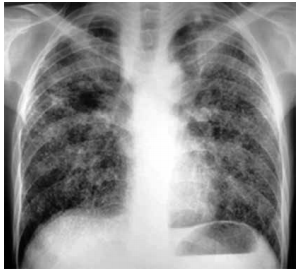

Paciente do sexo masculino, 42 anos, proveniente do

Ceará, procura atendimento médico por dispneia de longa data, mais intensa nos últimos 3 meses. Refere que

há 22 anos trabalha escavando poços de água potável.

Seu estado geral é bom, não há queixa de febre ou de

outros sintomas associados.

Analise a radiografia de tórax, ilustrada a seguir, e assinale a alternativa que contém a hipótese diagnóstica correta para o caso relatado.